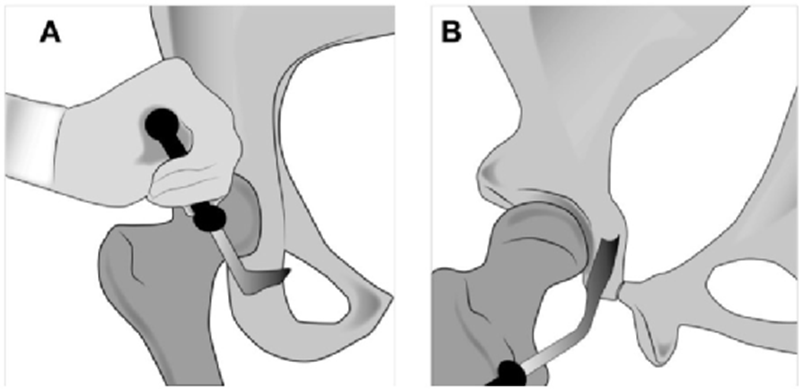

A.图显示用倾斜的Ganz骨刀进行髋臼下截骨。B.后柱的侧视图,显示向坐骨棘倾斜的不完整坐骨截骨。需要多次内侧和外侧击打确认截断整个厚度的坐骨。在截骨过程中伸展下肢,保护坐骨神经

A.耻骨截骨线位于耻骨跟部内侧几毫米处向内倾斜。B.内侧骨撬插入耻骨,近端与远端骨撬插入闭孔,以保护闭孔神经血管束。虚线显示截骨的位置。

A.图示髋臼上截骨,其指向坐骨大切迹,在骨盆缘1cm处停止。B.坐骨截骨,沿骨盆內缘保留后柱截骨。